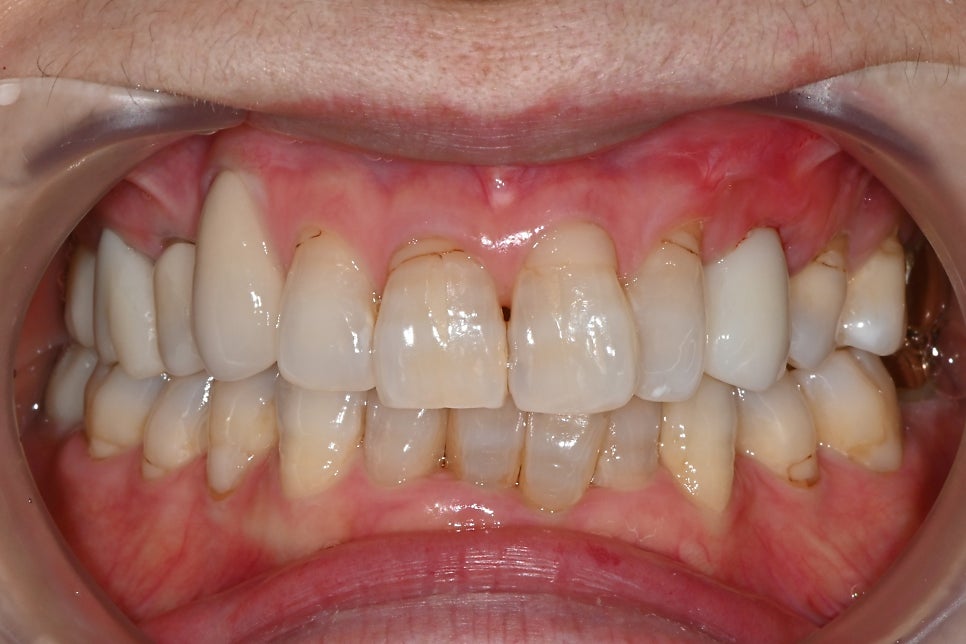

📸 Final front tooth prosthesis

Front-view photo of the completed front tooth implant

As requested by the patient, we completed it naturally with a slightly brighter tone,

and she was very satisfied with the result!